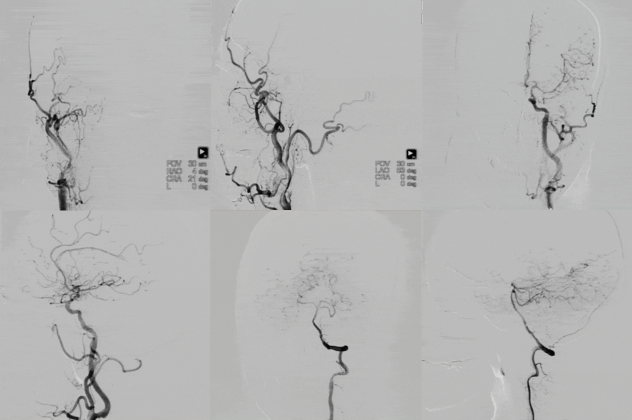

Right femoral artery access was obtained, and an 8F femoral sheath was inserted. Angiography revealed complete occlusion of the right ICA from the C1 segment to the intracranial portion. Collateral circulation to the right ICA territory was provided via the ophthalmic artery from the right external carotid artery. The anterior communicating artery was not visualized. The vertebral artery supplied the ICA territory through the posterior communicating artery.

Final angiography in both anteroposterior and lateral projections confirmed restored flow through the right ICA, with good opacification of both the MCA and ACA, without flow limitation.